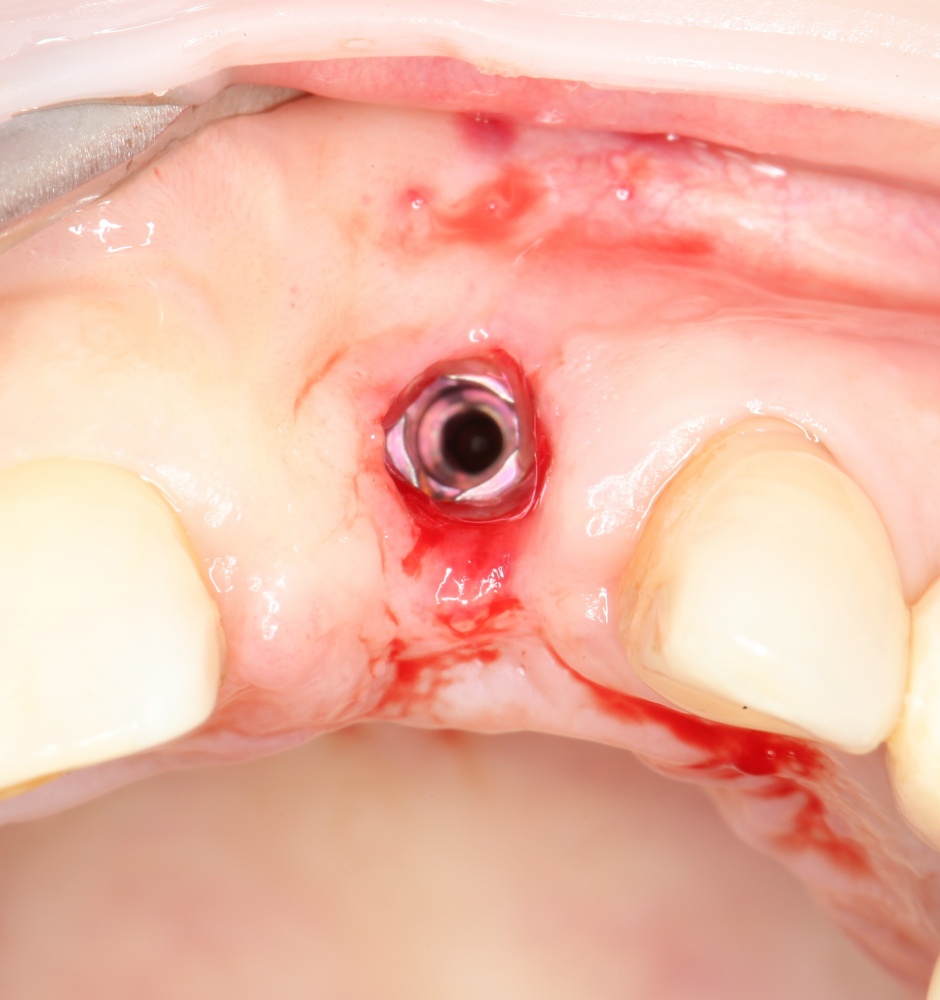

Рекомендации по установке имплантов. Для всех. Часть V.